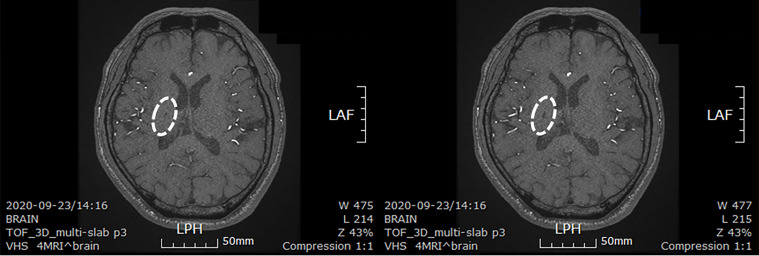

患者在干細(xì)胞移植后約30個(gè)月拍攝腦部CT圖像以確認(rèn)病灶的大小。病灶縮小至0.6cm×0.3cm(圖4)。